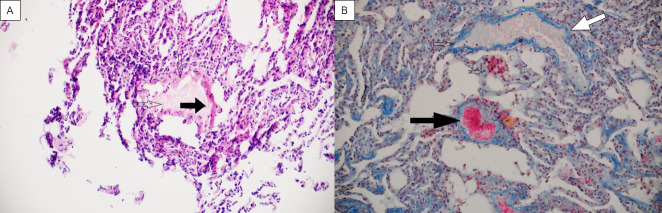

Methods: In this cross-sectional study, transbronchial lung biopsy was performed in long-COVID patients with persisting symptoms and radiological abnormalities. Histopathologic analyses were performed by using hematoxylin-eosin, Martius, Scarlet and Blue, Movat's, thyroid transcription factor 1, CD34, and CD68 staining.

Results: Adequate biopsy samples were obtained from 29/32 patients. The median (Q1-Q3) time from disease onset to biopsy was 13 (9-20) weeks. We observed several histopathologic patterns: DAD with vascular abnormalities (VA) (n=8); VA with inflammatory pattern (n=4); inflammatory pattern (n=13), and fibrotic pattern (n=4). VA included capillary thrombi, dilated venules, and dissection of small pulmonary arteries. DAD with VA was detected up to the 9th week from the onset of disease; inflammatory pattern from the 8th to 28th week (4 patients with this pattern biopsied in the 11th-13th week had accompanying VA); and a predominantly fibrotic pattern was found at weeks 8, 10, 48, and 49.

Conclusion: Our study observed a slow recovery of lung tissue with long-lasting DAD and VA, likely followed by interstitial inflammation or focal fibrosis. These findings might be the underlying cause of the slow recovery of long-COVID patients.